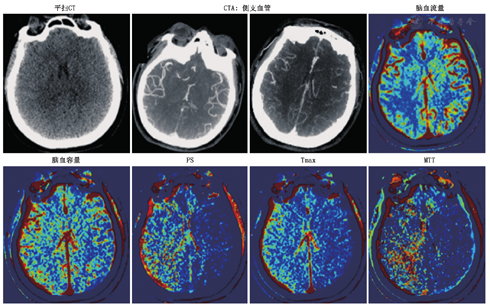

CTP是静脉快速团注对比剂,对感兴趣区层面进行连续扫描,获得感兴趣区时间/密度曲线,采用不同数学模型计算出不同的灌注参数值[12],包括:脑血流量(cerebral blood flow)、脑血容量(cerebral blood volume)、平均通过时间(mean transit time,MTT)、达峰时间(time to peak)、残余功能的达峰时间(time to peak of the deconvolved tissue residue function,Tmax)、表面通透性(permeability-surface area product,PS),详见图3。

脑血流量:指单位时间内脑组织的血供情况,可反映脑梗死组织的神经元活性;脑血容量:指目标区域内的全部血容量,可提示梗死核心的大小;MTT:指血流通过血管的平均时间;达峰时间:指脑血流量达到最大值的时间,可间接反映脑灌注的情况;Tmax:指组织储存功能达到最大值的时间,是反映组织灌注改变及脑组织梗死的敏感指标,常用来反映半暗带的指标和血脑屏障的完整性。与达峰时间不同,Tmax不受急性缺血性卒中的严重影响,可反映局部毛细血管水平的血流动力学变化,二者是在相同的灌注成像上通过不同的数学模型运算得到的结果。脑血流量、脑血容量、MTT、达峰时间或Tmax通常用于检测缺血半暗带或判断缺血高危组织损伤的严重程度或血脑屏障的完整性。在急性脑卒中的评估中,MTT或达峰时间等基于时间的参数会被延长,脑血流量在核心和半暗带区内均会减少。脑血容量可用于区分这些区域,即半暗带区侧支血管扩张引起的脑血容量增加,梗死中心内脑血容量减少。Tmax和PS可以帮助判断血脑屏障的完整性[13,14]。

"一站式"多模态CT由NCCT、CTP及CTA组成(图13),目前应用广泛,方便快捷,为动脉取栓、动脉瘤介入或外科手术提供精准诊疗。NCCT可鉴别患者是否存在脑出血;CTA可以鉴别是否有动脉瘤或大血管闭塞;CTP可以提供脑血流的灌注情况、是否存在半暗带、侧支循环及血脑屏障完整性等信息,为进一步制定患者的诊疗方案,判断预后奠定基础。